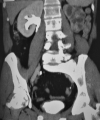

Results: Patient 1: A 58-year-old female had five episodes of acute left ureteral lithiasis in two years prior to left kidney tuberculosis. Patient 2: A 55-year-old male patient had a 1.2 cm proximal left ureteral stone and in the following six months, the diagnosis of tuberculosis was made in a nonfunctioning left kidney with ureteral thickening and stenosis. Patient 3: A 47-year-old male patient had a 1.2 cm stone in the proximal right ureter and developed urinary tuberculosis with a nonfunctioning right kidney and a contracted bladder.